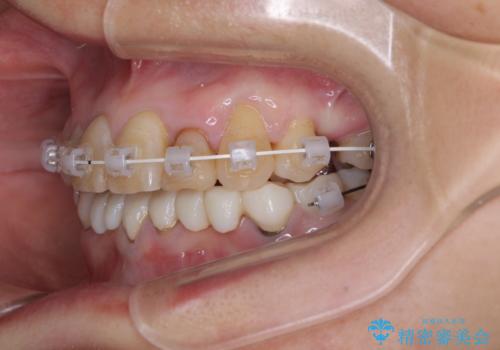

- 常に外れている下顎のブリッジと、前歯のデコボコと色を気にして来院された患者様です。

前歯のデコボコおよび奥歯の咬み合わせを改善するために、上顎左右の小臼歯を欠損スペースを利用して歯列を整え、矯正治療後に気になる上下前歯などをオールセラミッククラウンで美しく仕上げていくこととしました。